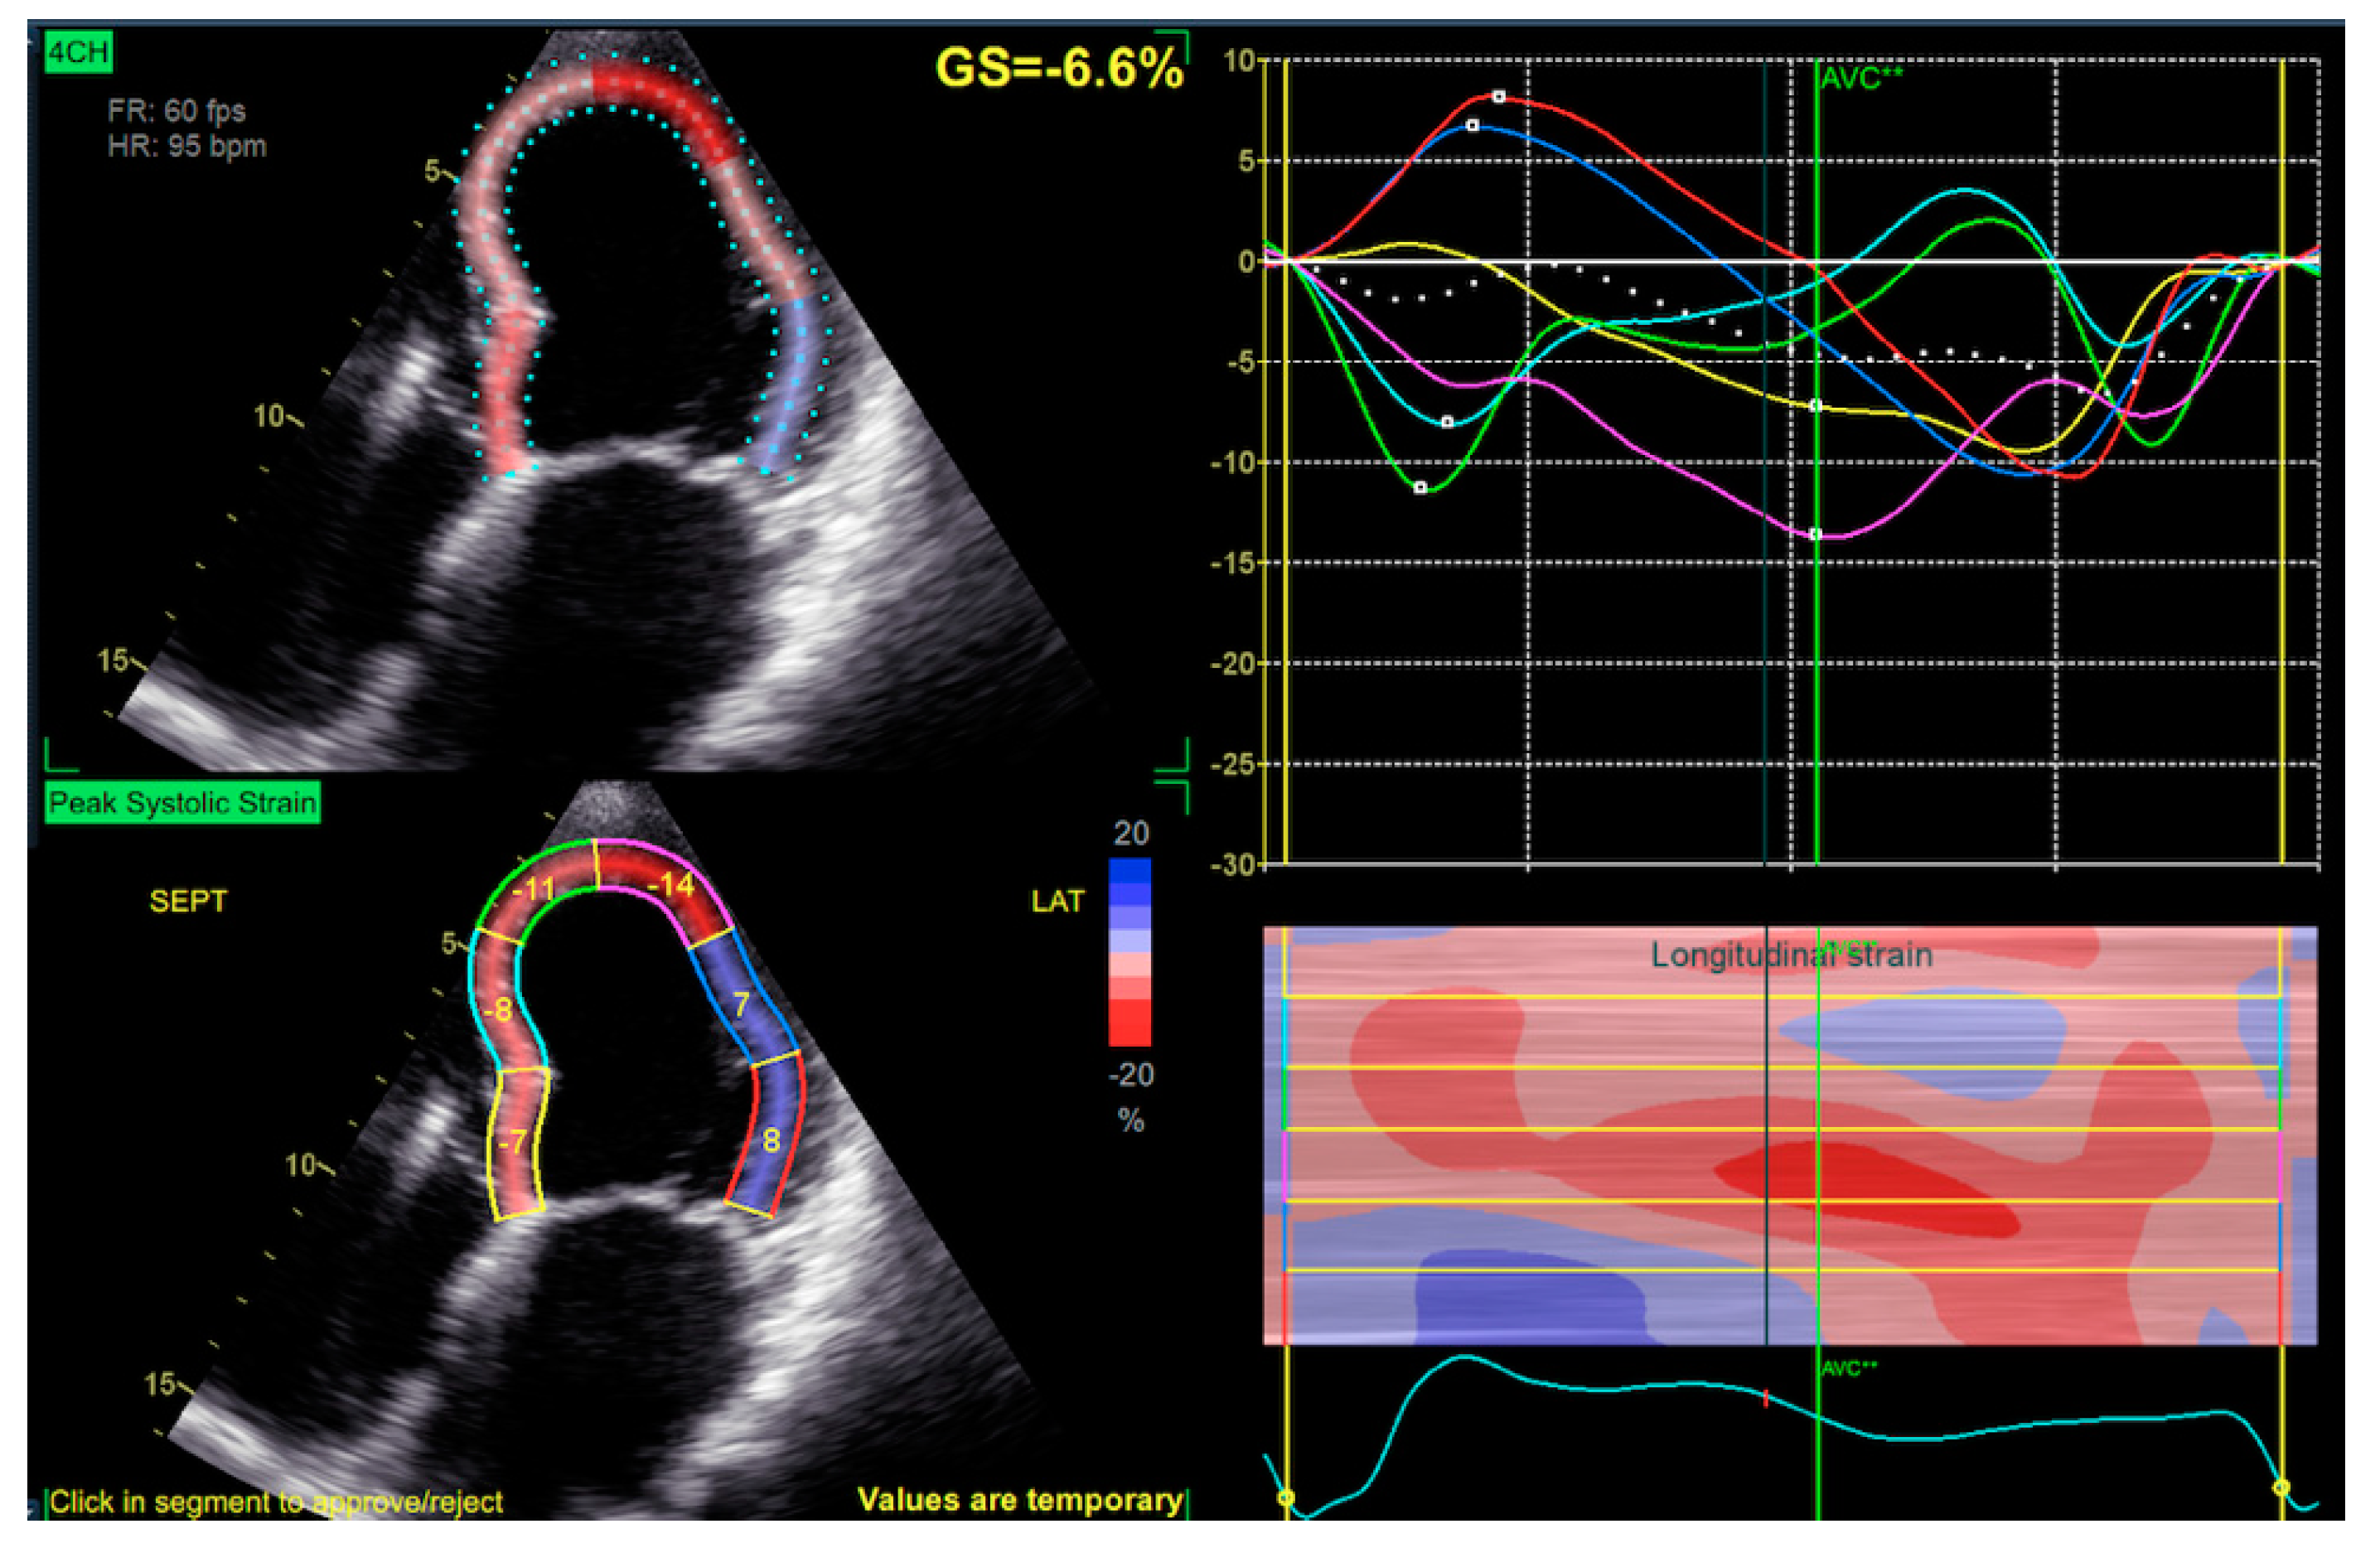

2.2. Echocardiography